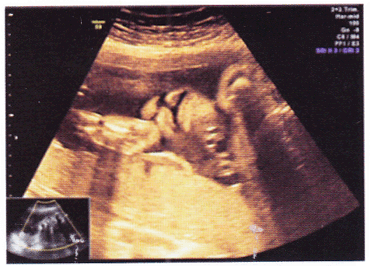

胎儿超声检查如图,最可能的诊断是 YZ434_ct_8_1.gif

题型: 单选题 分类: 超声波医学

• A.正常声像图

• B.淋巴管囊肿

• C.下腭裂

• D.唇裂

• E.以上腭裂